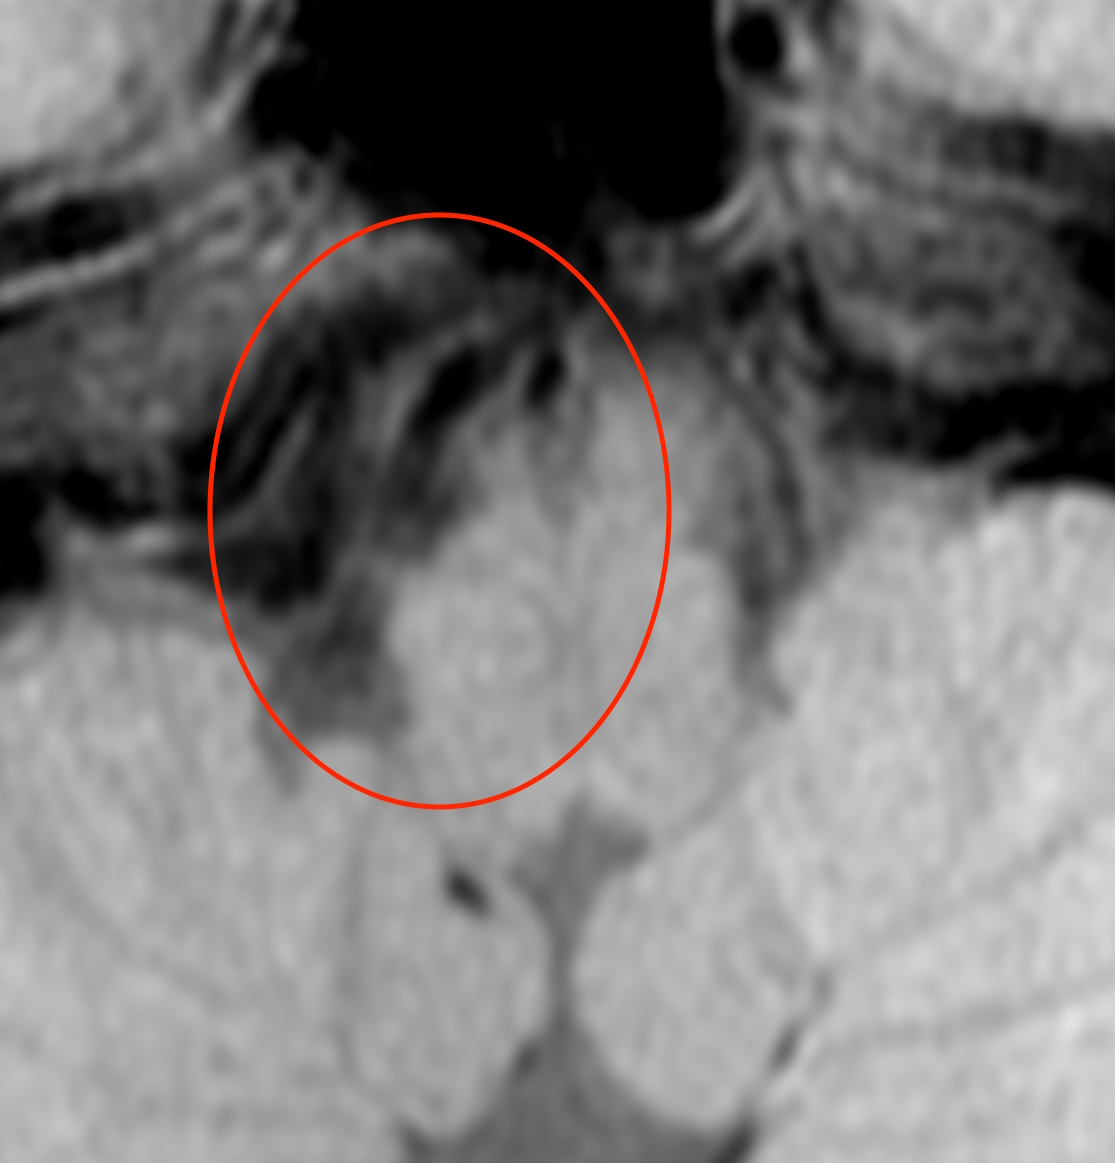

※椎骨動脈解離では、下のように血管のくびれや膨らみが見られます。

しかし、椎骨動脈解離の場合には、T1BB法(T1 black blood method)という特殊な撮像法を行うと、

このように血管壁にできた血栓(血液の固まり)が白く写ります。